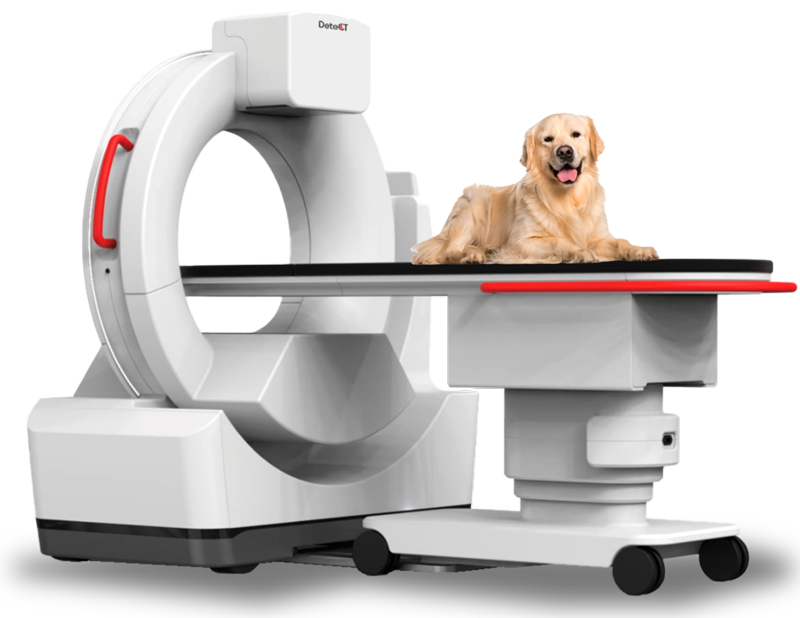

- Tomografía Computarizada.